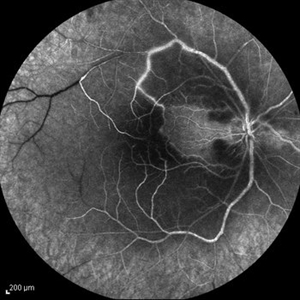

Behcet's Disease Behcet's DiseaseMar 13 2013 by Hamid Ahmadieh, MD Early phase FA of the right eye of a 23-year-old man with retinal vasculitis and branch retinal vein occlusion (BRVO) due to Behcet's disease . Photographer: Solmaz Shahmohammad, Negah Eye Center, Tehran Imaging device: Heidelberg Spectralis Condition/keywords: branch retinal vein occlusion (BRVO), retinal vasculitis